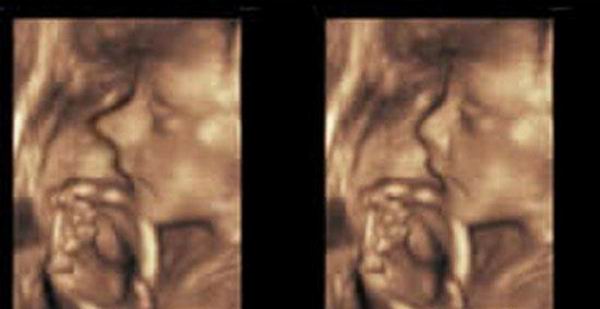

Корректировка носа еще не родившегося ребенка

Внешность достается ребенку от смешения генетических особенностей его родителей. И часто бывает, что выдающиеся черты лица мамы или папы передаются их детям. И далеко не всегда речь идет о наследственной красоте, ведь бывают и наследственные уродства. Обычно пластические хирурги борются с ними, когда человек достигает сознательного возраста, но бывают также удивительные исключения.

В качестве примера можно привести случай, произошедший несколько лет назад в Беверли Хиллз. Беременная мать обратилась к пластическим хирургам с просьбой сделать операцию ее еще не родившемуся сыну. Ведь ультразвуковое исследование плода показало, что мальчик, судя по всему, унаследует ужасно длинный нос от своего родителя. Так почему бы не избавить ребенка от этого уродства в самом раннем возрасте?

Интересно, что врачи после определенных раздумий согласились провести данную операцию. Они решили, что питательная среда в утробе матери позитивно повлияет на шрамы после хирургического вмешательства, и к моменту рождения ребенка от них не останется никаких следов.

Операция прошла успешно.